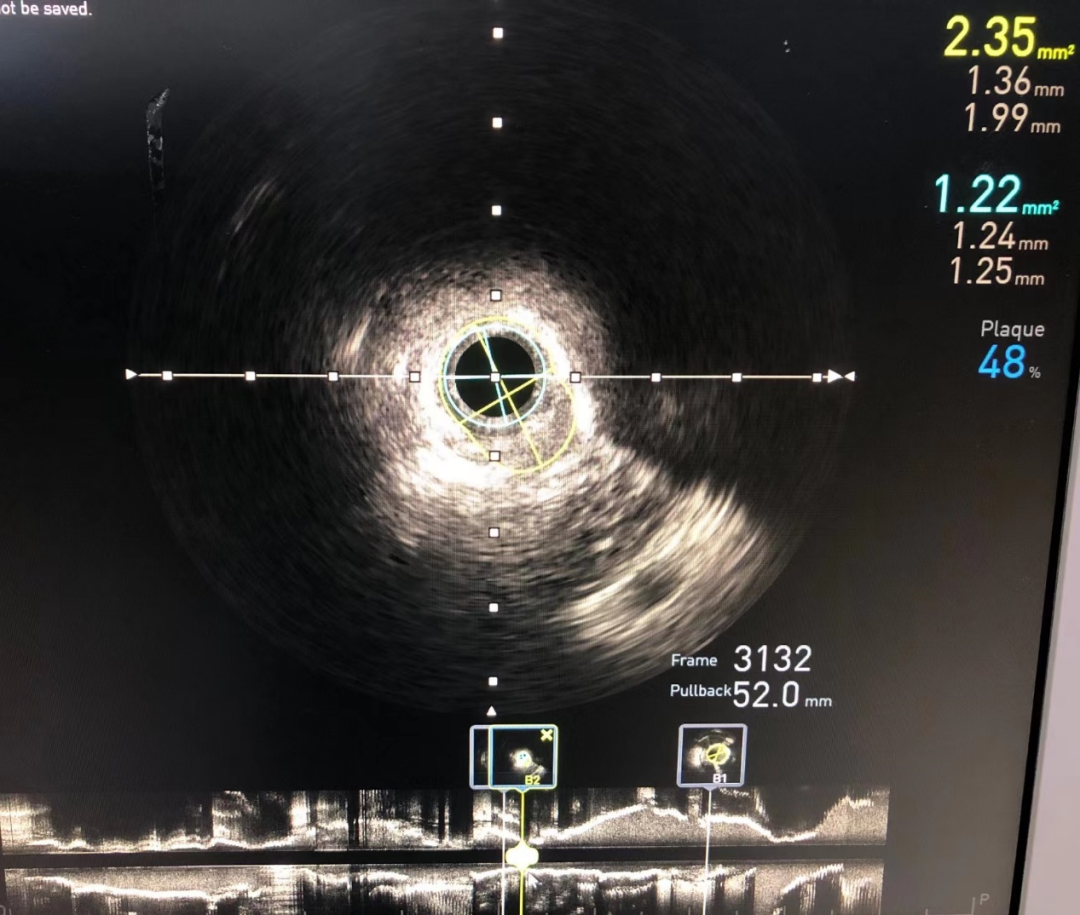

IVUS提示左前降支-左主干弥漫动脉粥样硬化斑块形成,多处严重内膜环形钙化,血管管腔直径在3.5mm以上,其中最严重的地方,血管管腔面积仅2.35mm²。

术前IVUS影像,MLA 2.35mm²